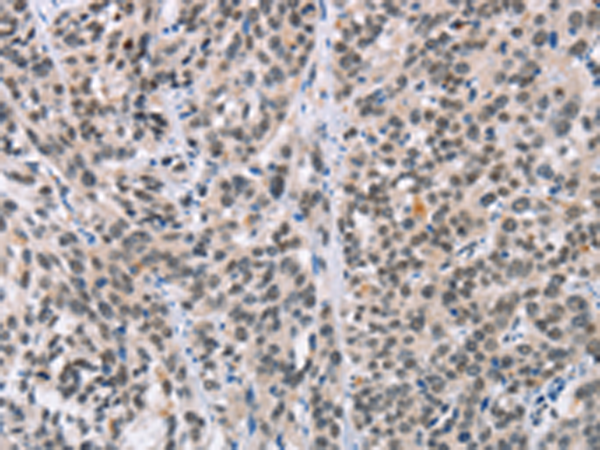

分类: 科研抗体货号: P11573别名: HYDM; PAN7; NALP7; NOD12; PYPAF3; CLR19.4应用: IHC反应种属: Human